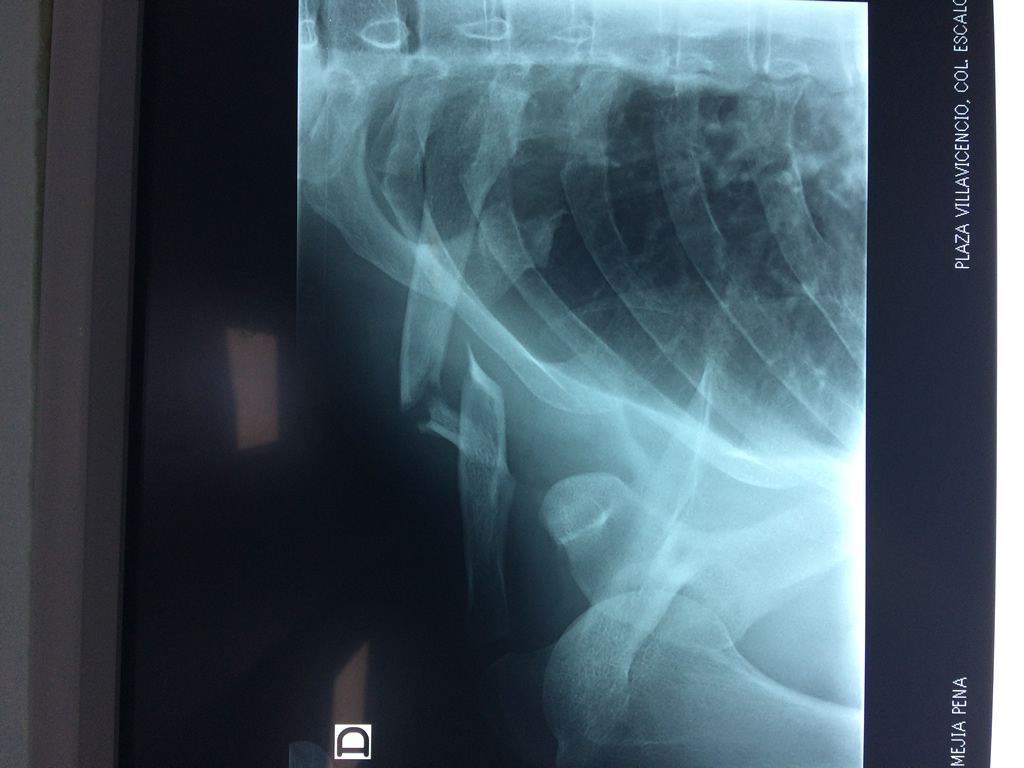

Cirugías de Calcaneo - Clavícula

La clavícula es un hueso largo, con forma de "S" itálica, situado en la parte anterosuperior del tórax. Junto con la escápula forman la cintura escapular. Se puede palpar por toda su longitud y se extiende del esternón al acromion de la escápula, siguiendo una dirección oblicua lateral y posterior.